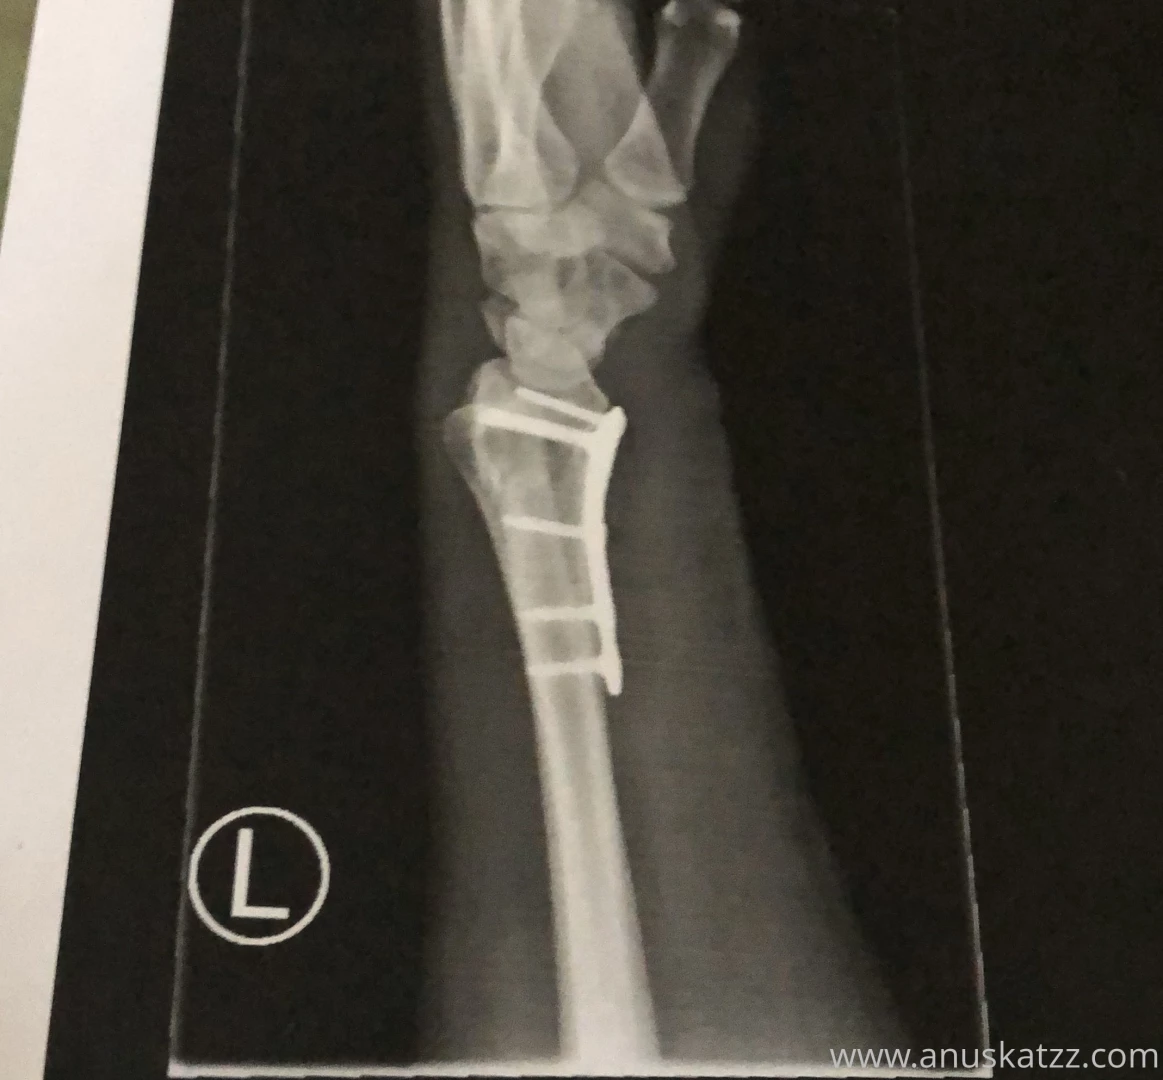

I got a titan plate stuck to my bones who help me heal the broken arm I got them implemented trough operation who is now 3 days ago The pain is unbelievable I feel the unnatural connection between bone and plate it directly send the pain to my big scare on the side of my arm I hope I will heal fast and my body will be strong enough for this intense intervention Next week I have again an appointment in the hospital to see if everthing work properly